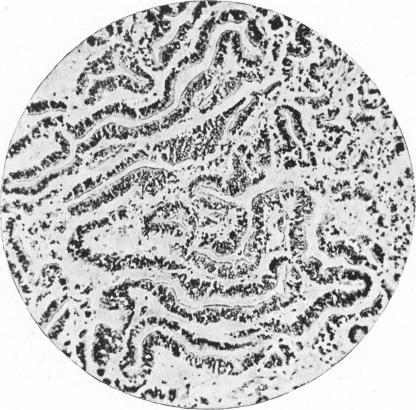

A Case of Papilloma of the Choroid Plexus.

Arch Dis Child. 1933 Feb;8(43):53-6. doi: 10.1136/adc.8.43.53.

A Case of Papilloma of the Choroid Plexus.一例脉络丛乳头状瘤病例。